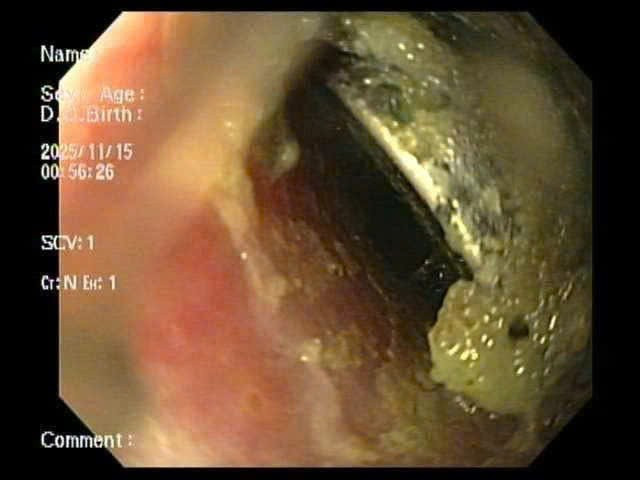

Kết quả X-quang cho thấy dị vật mắc lại ở thực quản. Các bác sĩ tiến hành nội soi cấp cứu và gắp thành công viên pin. Tuy nhiên, quan sát trực tiếp tại vị trí mắc cho thấy vùng thực quản đã bị ăn mòn và loét lớn - minh chứng pin cúc áo có thể gây tổn thương nặng nề chỉ trong thời gian rất ngắn, dù trẻ được đưa đến viện sớm.

Hình ảnh viên pin cúc trong thực quản bệnh nhi. Ảnh: Bệnh viện Nhi Hải Phòng